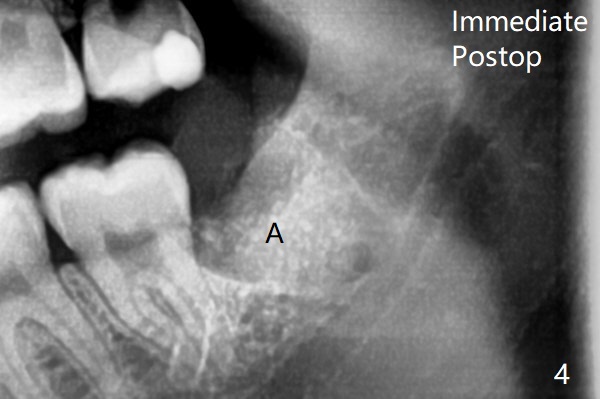

18岁时三角形变大,密度增高(图二)。其实术中发现外斜嵴两侧都不明显(女孩原因?),拔除两侧都需要颊侧去骨。由于左侧智齿颊侧阻生(图三:*),拔除后两侧都放置骨水泥(Bond Apatite,图四:A)促进骨修复,口腔卫生欠缺,可能容易形成牙周炎。